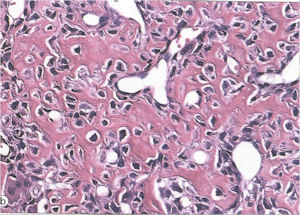

- Interlacing network of bone trabeculae in a loose fibrovascular stroma

- Prominent vessels

- Osteoblasts are plump, active, scattered mitotic figures

- Osteoblasts line up around periphery of trabeculae (Osteoblastic Rimming)

- Soft tissue component usually surrounded by shell of reactive bone or periosteum (Egg Shell Rim of Calcification)

- No cartilage production (as opposed to osteosarcomas that may contain areas of cartilage)